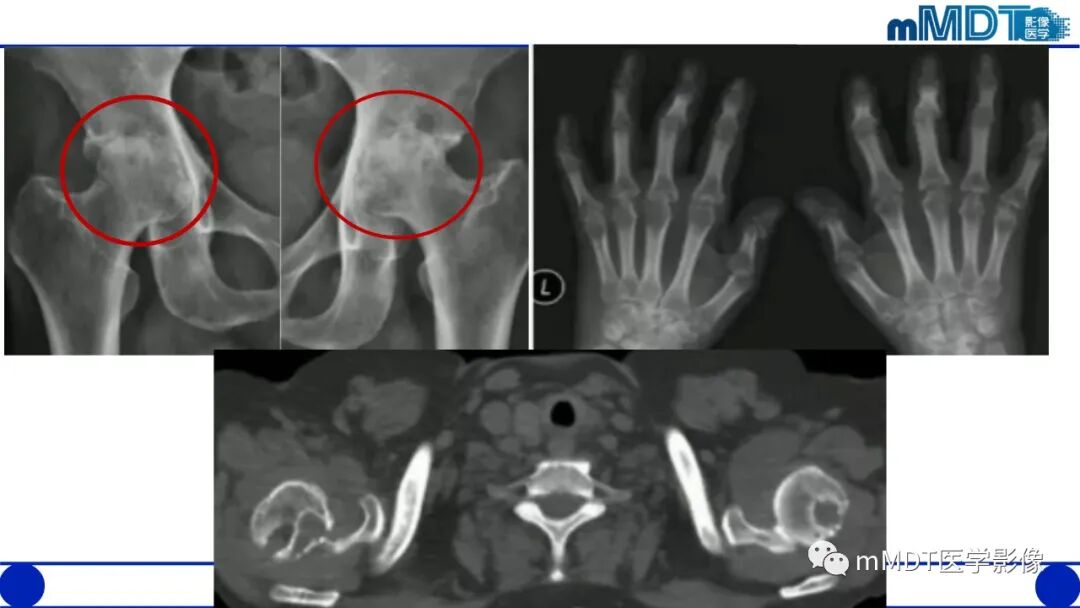

1.X线平片对本病的诊断是重要的,还应作相关测量,包括髋臼角、CE角、髋臼覆盖率(股骨头裸露程度)等。成人以测量CE角较为准确,而且简便。

2.在骨盆前后位片上髋臼顶短小,CE角小于30度,伴或不伴有髋臼倾斜度过大(髋臼角大于45度),股骨头裸露25%以上,可诊断为髋臼发育不良。需要注意的是,有时髋臼边缘继发骨性增生,使髋臼外缘代偿性加宽(假臼缘形成),可表现为CE角减小不明显甚至不变小;而股骨头肥大、变形、外移或半脱位时则可出现由于股骨头中心外移造成的CE角过度变小和股骨头裸露增大,在这种情况下,观察髋臼角的增大及髋臼深度的改变有重要意义。